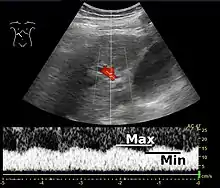

Portal vein pulsatility can be measured by Doppler ultrasonography. An increased pulsatility may be caused by cirrhosis, as well as increased right atrial pressure (which in turn may be caused by right heart failure or tricuspid regurgitation).[9] Portal vein pulsatility can be quantified by pulsatility indices (PI), where an index above a certain cutoff indicates pathology:

| Average-based | (Max - Min) / Average[9] | 0.5[9] |

| Max-based | (Max - Min) / Max[11] | 0.5[11][12] - 0.54[12] |